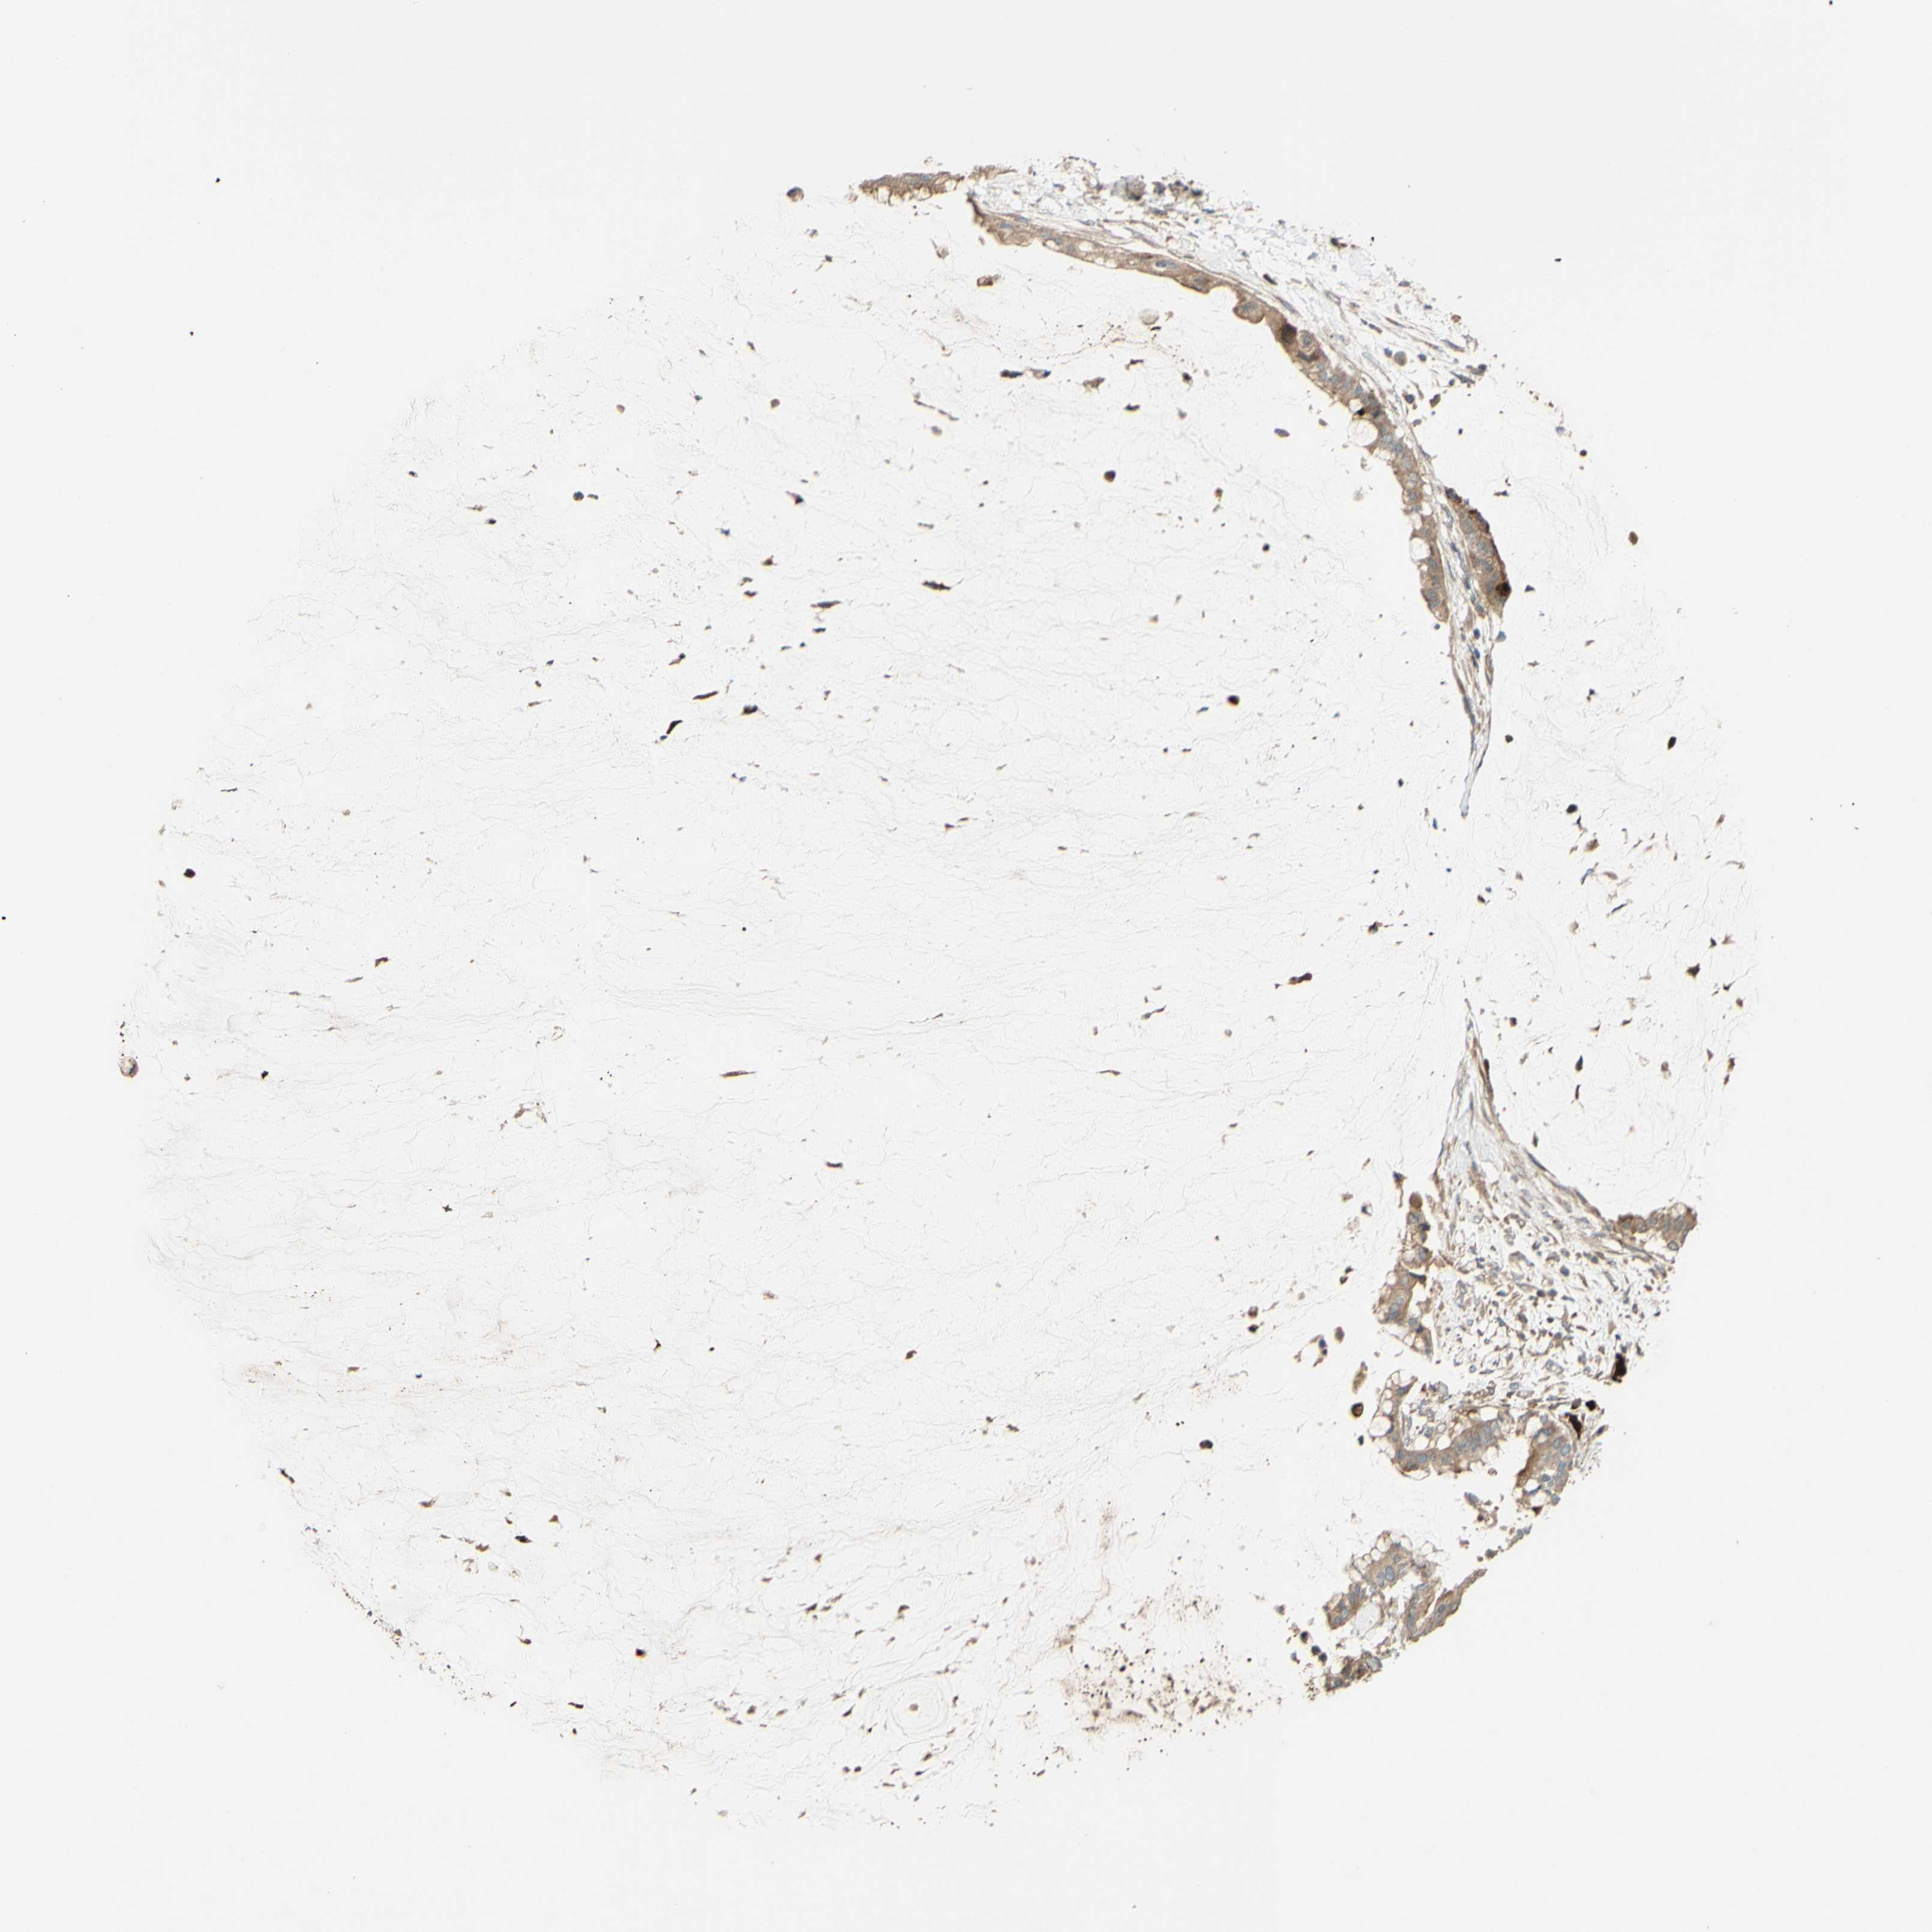

PANCREATIC CANCER - Protein expressioni

A mouse-over function shows sample information and annotation data. Click on an image to view it in a full screen mode. Samples can be filtered based on level of antibody staining by selecting one or several of the following categories: high, medium, low and not detected. The assay and annotation is described here.

Note that samples used for immunohistochemistry by the Human Protein Atlas do not correspond to samples in the TCGA dataset.

Antibody stainingi

Antibody staining in the annotated cell types in the current human tissue is reported as not detected, low, medium, or high, based on conventional immunohistochemistry profiling in selected tissues. This score is based on the combination of the staining intensity and fraction of stained cells.

Each image is clickable and will lead to virtual microscopy that enables deeper exploration of all samples and also displays staining intensity scores, fraction scores and subcellular localization as well as patient and tissue information for each sample.

Antibody HPA023652

Antibody CAB011455

Staining

High

Medium

Low

Not detected

Intensity

Strong

Moderate

Weak

Negative

Quantity

>75%

75%-25%

<25%

None

Location

Nuclear

Cytoplasmic/membranous

Cytoplasmic/membranous,nuclear

Adenocarcinoma, NOS

Adenocarcinoma, metastatic, NOS